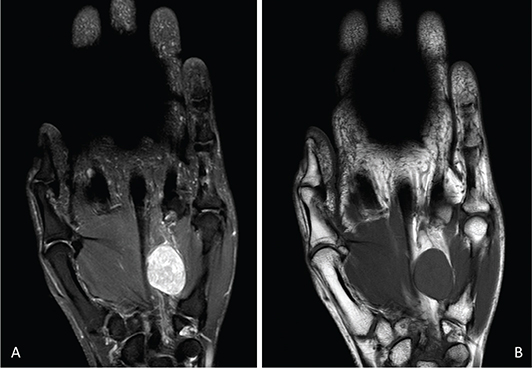

On examination, a firm, mobile nodule was palpable. Palpation elicited mild numbness in the ulnar digits and discomfort radiating across the hand (Figure 3). Ultrasound imaging revealed a well-encapsulated lesion adjacent to the ulnar nerve in the distal segment of Guyon’s canal. MRI demonstrated a hyperintense signal on T2-weighted sequences and an isointense signal on T1-weighted sequences (Figure 4). Following informed consent, surgical excision was performed.

Figure 4. On MRI, the schwannoma appears: (A) hyperintense relative to muscle on T2-weighted sequences and (B) isointense on T1-weighted sequences. MRI: magnetic resonance imaging.